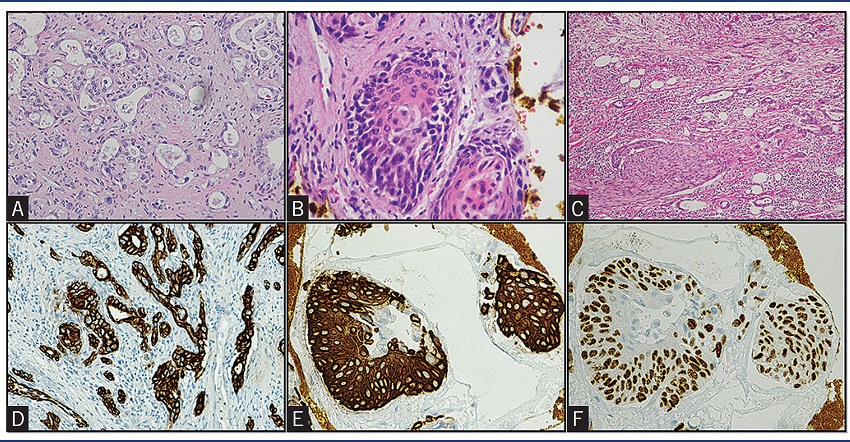

The tumors were formed by a double component, glandular and squamous, intermixed in a desmoplastic stroma. The first was represented by glands in a cribriform or isolated pattern, with slightly pleomorphic cells and grumpy chromatin (Figure 3A); the latter presented trabecular/solid architecture with polygonal and pleomorphic cells, with eosinophil cytoplasm, loss of nuclear polarity and visible nucleoli, dyskeratotic cells and keratin pearls (Figure 3B). The tumors had high mitotic activity, including atypical forms. All had neural and vascular invasion (Figure 3C), as well as lymph node metastasis. In one patient there was also lymph node involvement by diffuse large B-cell lymphoma, previously diagnosed.

A) HE 200x, glandular component; B) HE 400x, squamous component; C) HE 100x, neural invasion; D) CK7 immunostaining 200x, highlighting the glandular component; E) CK5/6 400x, immunolabeling in the squamous component; F) P63 400x, nuclei staining in the squamous component cells.

HE: hematoxylin and eosin.

The glandular component was positive for CK7 (Figure 3D) and the squamous component was reactive for CK5/6 (Figure 3E) and p63 (Figure 3F).